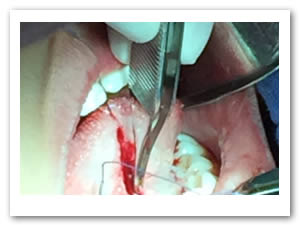

• Se colocó anestesia tópica y se infiltró localmente (lidocaína con epinefrina de 1: 100 000 al 2 %) a cada lado del frenillo lingual bloqueando nervio lingual bilateralmente. (Figuras 1 y 2).

Figura 1. Anestesia Local a cada lado del frenillo.

Figura 2. Anestesia Local del nervio lingual bilateralmente